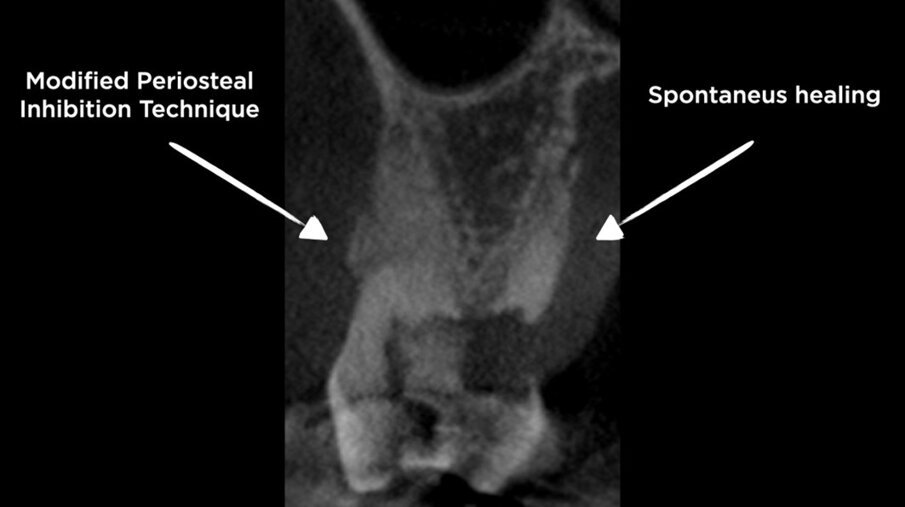

La CBCT dopo 4 mesi ha mostrato il mantenimento della corticale vestibolare (Figg. 7a, 7b), e anche un aumento della dimensione bucco-linguale (Fig. 8). Sul lato palatale, dove il sito è guarito naturalmente, la parete palatale ha subito un normale rimodellamento. Le immagini CBCT mostrano chiaramente la capacità della lamina corticale di inibire il riassorbimento della corticale buccale e di sostituirla o sostenerla. Ciò suggerirebbe che la lamina potrebbe essere utilizzata al posto di una membrana D-PTFE per ottenere un risultato ancora migliore rispetto alla classica tecnica di inibizione periostale, considerando anche che la lamina si integra nel sito8, 9 e non richiede una procedura di rientro. La guarigione è avvenuta senza complicazioni e il volume osseo creato era sufficiente per posizionare un impianto standard da 4,1 mm (Figg. 9, 10).

Figg. 7a, 7b - CBCT dopo Inibizione Periostale Modificata.